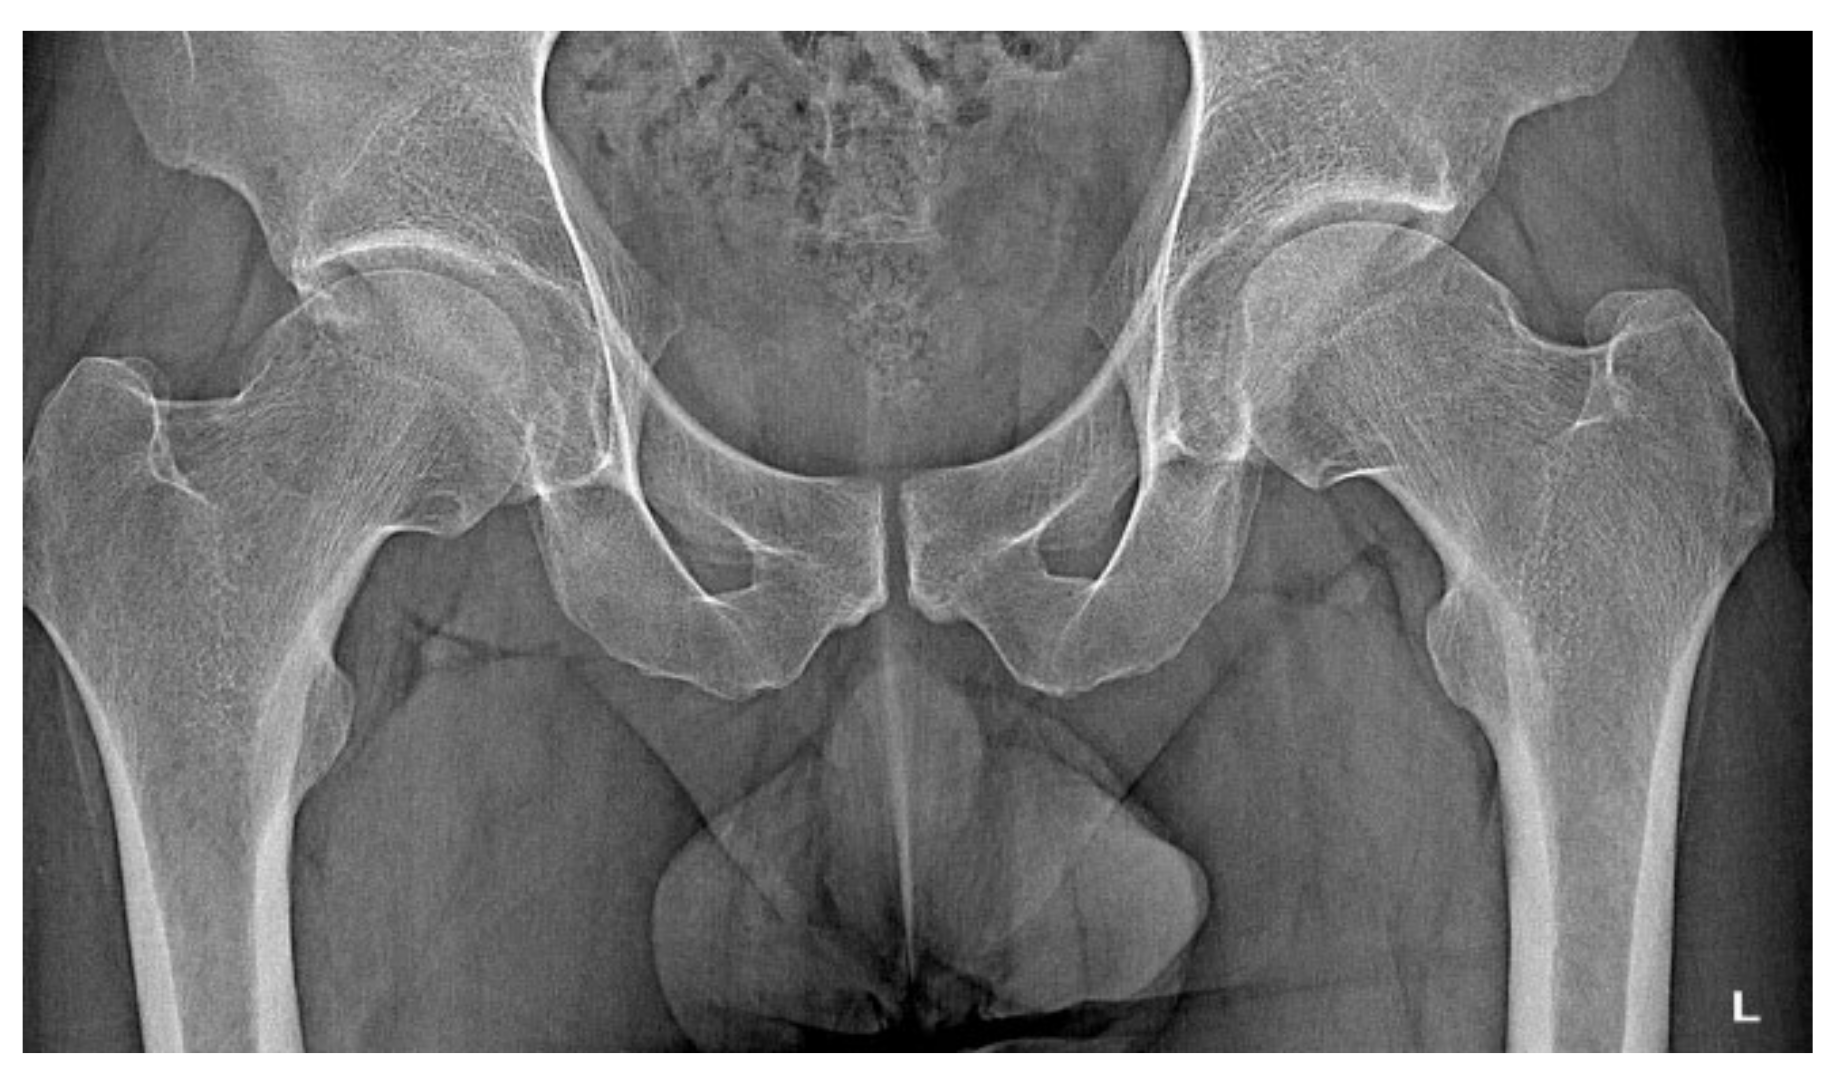

A 30-year-old man was operated on for OO of the right femoral neck. He had a history of night and post-exercise pain in the right hip for 6 months. On physical examination, positive femoroacetabular impingement-specific tests, FADIR (groin pain on flexion, internal rotation and successive adduction of the hip joint) and FABER (groin pain on flexion, external rotation and abduction of the hip joint) were carried out. After a pelvic X-ray and hip MRI scan, a diagnosis of femoroacetabular impingement was made, and the patient was qualified for arthroscopy (Figure 1). The imaging changes suggested a diagnosis of FAI. While awaiting arthroscopy, an ambiguous clinical picture with a history of night pain prompted the attending physician to perform a CT scan of the hip joints. The scan showed a focus of OO of 9 × 6 × 5 mm in the right femoral neck (Figure 2). The patient was treated with thermoablation with intraoperative 3D navigation at the temperature of 90 degrees for 6 min without complications during and after the procedure. An excellent VAS pain reduction score was achieved from 8 points on the day of surgery to 0 at 3 months after surgery. On physical examination 3 months after surgery, the FADIR and FABER tests were negative. The symptoms of FAI disappeared completely.

Figure 1.

X-ray examination of the hip joints with the features of FAI.